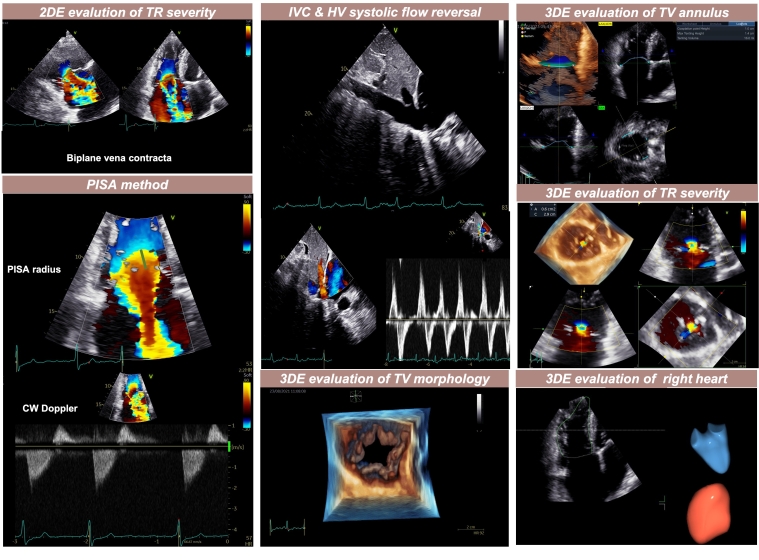

Advanced quantification of RV and RA volumes and function (three-dimensional [3D] echocardiography to assess ejection fraction, and myocardial deformation by speckle-tracking echocardiography to measure longitudinal strain) should be obtained and reported, whenever possible since conventional 2D indices have known limitations in assessing STR.  Therefore, it is recommended to include both 3D and speckle-tracking echocardiography in the standard evaluation protocol of patients with TR. This will allow for a more thorough evaluation of the TV’s complex morphology, including the number of leaflets, as well as for a better assessment of the severity of TR through the 3D vena contracta area, and of the impact of TR on right heart chambers (Central Figure).

Central illustration. Integrative assessment of tricuspid regurgitation with two- and three-dimensional echocardiography.

330_Muraru_CENTRAL FIGURE_escardio-hPhotoLarge.jpg2DE: two-dimensional echocardiography; TR: tricuspid regurgitation; PISA: proximal isovelocity surface area; CW: continuous wave; IVC: inferior vena cava; HV: hepatic vein; 3DE: three-dimensional echocardiography; TV: tricuspid valve